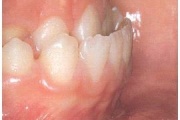

Vali sind huvitav pilt ja me näitame sellega seotud haigust ja sümptomeid